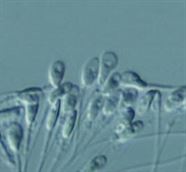

OPU esnasında toplanan yumurtaların embriyolog tarafından yumurtayı çevreleyen kümülüs hücrelerine bakılarak Kümülüs-Oosit Kompleksi (COC) değerlendirmesi yapılır.

Tip I ve Tip II (Matür) COC;

Kümülüs hücreleri ışınsal radyal dağılım gösterir.

Kümülüs kompleksi gevşek yapıdadır.

Korona radiata hücreleri hafif-kompakt görünümlüdür.

Granüloza hücreleri genişlemiş ve düzenli kümeler şeklinde görülür.

Perivitellin aralıkta birinci polar body belirgindir.

Ooplazma net olarak gözlenir.

Tip III-Tip IV (İmmatür) COC;

Kümülüs ve korona radiata hücreleri yoğun dağılım gösterir.

Granuloza hücreleri koyu renkli ve kompakt yapıdadır.

Bazı vakalarda dejenere/atretik veya boş zona oosit (Yumurtanın dış zarına sahip, ooplazmasız oosit) alınabilir.

1 : Dejenere / atretik oosit 2 : Empty zona oosit